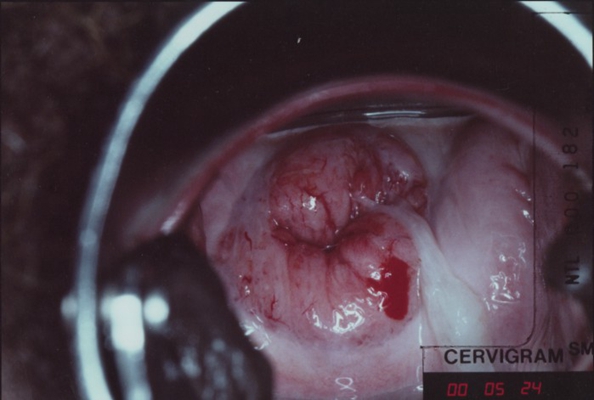

子宮頸癌圖片

宮頸癌

宮頸癌

宮頸癌

宮頸癌

宮頸癌

宮頸癌

宮頸癌

宮頸癌

宮頸癌

宮頸癌

宮頸癌

宮頸癌

宮頸癌

宮頸癌

宮頸癌

宮頸癌

宮頸癌

宮頸癌

宮頸癌

宮頸癌